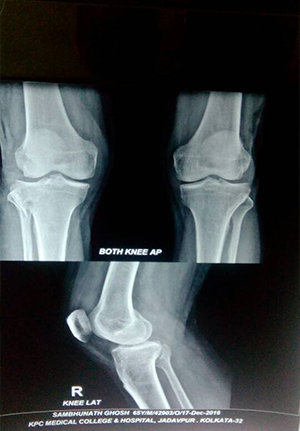

Reduction and internal fixation for proximal tibial fracture

before operation

After operation